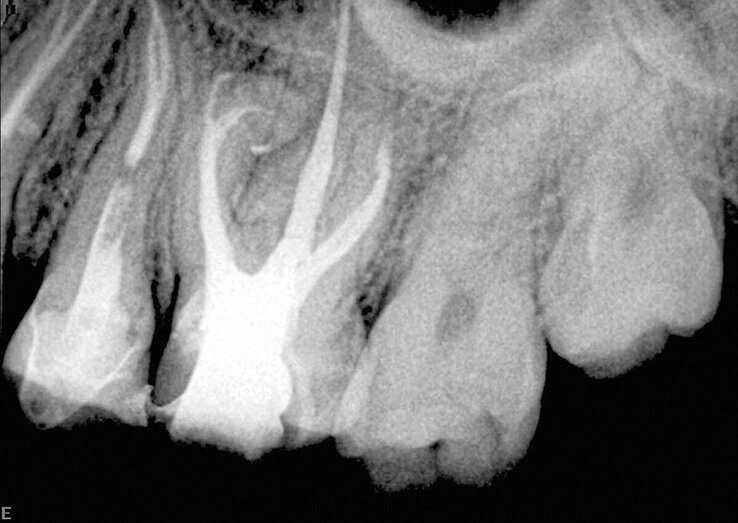

Slučaj 2 – Slika br. 4: Inicijalni periapikalni Rtg snimak

Slučaj 2 – Slika br. 5: Periapikalni kontrolni Rtg snimak odmah nakon tretmana

Pacijent je upućen na retretman donjeg molara. Početni rendgenski snimak prikazuje metalni liveni kočić u distalnom kanalu, separiran instrument u jednom od mezijalnih kanala i radiolucenciju na apeksu. Pacijent je obavešten da ću morati da mu uklonim staru krunicu i metalni kočić da bih mogao da uradim enododntski retretman i to će mi omogućiti pristup kanalima korena da ih ponovo obradim i napunim. Alternativa je da bila da uradim mikrohirurgiju na mezijalnom korenu, ali za ovo bih morao da isečem dugačak deo korena da bih postigao hermetičko zatvaranje unutar kanala zbog zalomljene turpije i nedostajućeg dela kanala koji nije tretiran. Pacijent je prihvatio prvi izbor. Prvi koraci su bili sečenje krunice i njeno uklanjanje, zatim sam nastavio sa delikatnim sečenjem metalnog kočića kako bi ga uklonili deo po deo. Deo zuba u kojem je kočić sam vibrirao ultrazvukom i bezbedno ga skidao. Ovo mi je omogućilo pristup gutaperki ispod. Koristio sam isti redosled turpija, Traverse i Zenflex. U distalnom korenu sam uspeo da idem sve do radne dužine, u mezio-bukalnom takođe do kraja, u mezio-lingvalnom sam stao gde je bila separiran isntrument. Ovde sam počeo da koristim male K-file turpije veličina 06 08 10 i 15 da zaobiđem instrument, imao sam sreće da to uradim pa čak i da je izvadim iz unutrašnjosti zakrivljenosti, i napravljeno je potpuno čišćenje i oblikovanje, praćeno 3D obturacijom sa elements IC (Slika br. 4). Jednogodišnje praćenje (Slika br. 5) pokazuje odlično izlečenje.